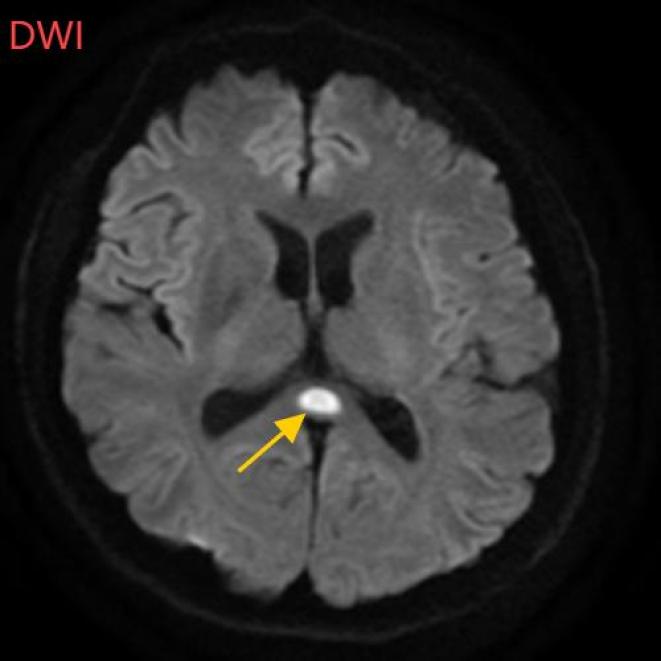

医生摇摇头。经过头部磁共振平扫、弥漫、增强图像等检查。,医生诊断,小董患有一种罕见的疾病:可逆性体压部综合征。

根据小董的影像数据,受压部位发生病变。

体压部病变被广泛认为与细胞毒性水肿有关,而水肿的诱因通常是由于大量饮酒导致维生素B1摄入受阻,辅酶缺乏。

经过一周的治疗,小董体压部病变明显改善。